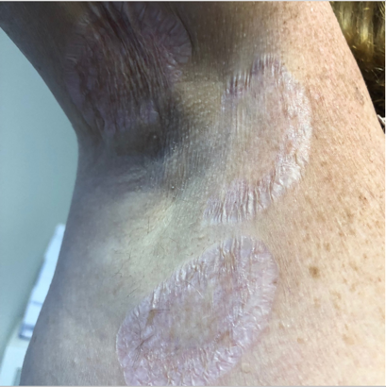

A 28-year-old woman presented to our clinic with hypopigmented, atrophic macules coalescing into large patches on the right lateral neck. The lesions initially started as scattered spots on the neck and subsequently spread to the right shoulder, right axilla, bilateral medial breasts, and abdomen (Figure 1). The patches were asymptomatic.

A physical examination revealed hypopigmented, annular, atrophic patches across the torso. The patient had no family history of similar lesions or known medical problems, was taking no medications, and denied trauma to the areas.

The initial clinical presentation of our patient suggested extragenital LSA given the morphology of the lesions and their characteristic distribution. The patient did not have genital involvement. However, other diagnoses were considered, and a skin biopsy was performed.